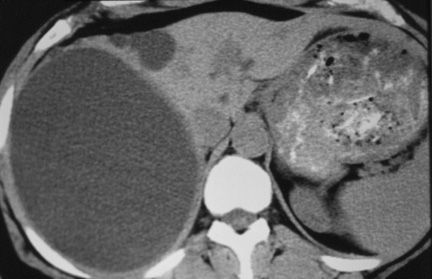

Theo phân loại nang gan, thường gặp nhất là nang gan đơn độc và bệnh đa nang (thường có nhiều nang ở gan và thận). Ít gặp hơn là nang gan do ký sinh trùng (do Echinococcus), U nang tuyến, nang đường mật,... và hiếm gặp hơn là các tổn thương ung thư dạng nang như ung thư biểu mô tế bào vảy, ung thư biểu mô nang tuyến, ung thư di căn,... và các tổn thương giả nang như xuất huyết trong gan do chấn thương, nhồi máu gan,...

Xét nghiệm hình ảnh: chụp cắt lớp vi tính (CT Scan), chụp cộng hưởng từ (MRI), siêu âm.